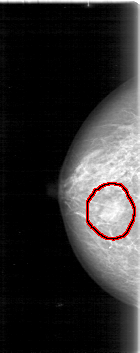

D_4012_1.RIGHT_MLO

LEFT_MLO LINES 5386 PIXELS_PER_LINE 2341 BITS_PER_PIXEL 12 RESOLUTION 43.5 NON_OVERLAY

FILE: D_4012_1.RIGHT_MLO.OVERLAY

TOTAL_ABNORMALITIES 1

ABNORMALITY 1

LESION_TYPE MASS SHAPE OVAL MARGINS OBSCURED

ASSESSMENT 0

SUBTLETY 5

PATHOLOGY BENIGN

TOTAL_OUTLINES 1

BOUNDARY